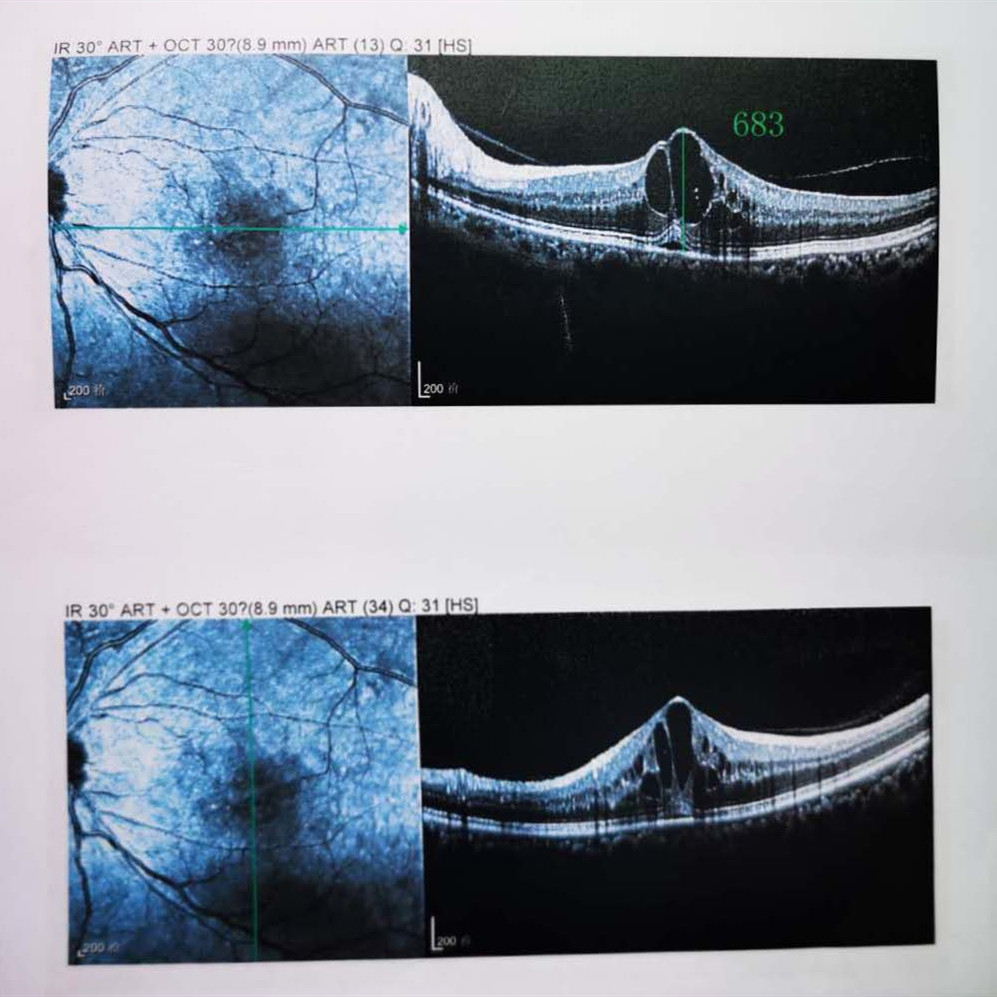

檢查結(jié)果顯示,武先生并沒有近視,右眼視力為1.0,但是左眼視力只有0.4,而且左眼視網(wǎng)膜各分支靜脈迂曲擴(kuò)張,全網(wǎng)膜面見火焰狀出血,黃斑區(qū)高度水腫、滲出,黃斑中心凹厚度約683um。

(武先生初次就診眼底OCT檢查圖)

而正常的矯正視力是1.0,黃斑中心凹厚度在200um左右。

“你這黃斑都腫到正常人的三四倍大了!”廈門眼科中心吳國(guó)基院長(zhǎng)醫(yī)生告訴武先生,“你這是左眼視網(wǎng)膜中央靜脈阻塞伴黃斑水腫,你左眼的視力下降、看東西變形,是因?yàn)槟阕笱垡暰W(wǎng)膜的中央靜脈發(fā)生了阻塞、出血,導(dǎo)致眼底黃斑水腫了。”

那么,武先生的視力恢復(fù)情況如何呢?幸運(yùn)的是,經(jīng)過(guò)兩次玻璃體腔注藥術(shù),武先生左眼的黃斑水腫得到明顯改善,視力已經(jīng)恢復(fù)到0.8。

(武先生出院時(shí)眼底OCT檢查圖)